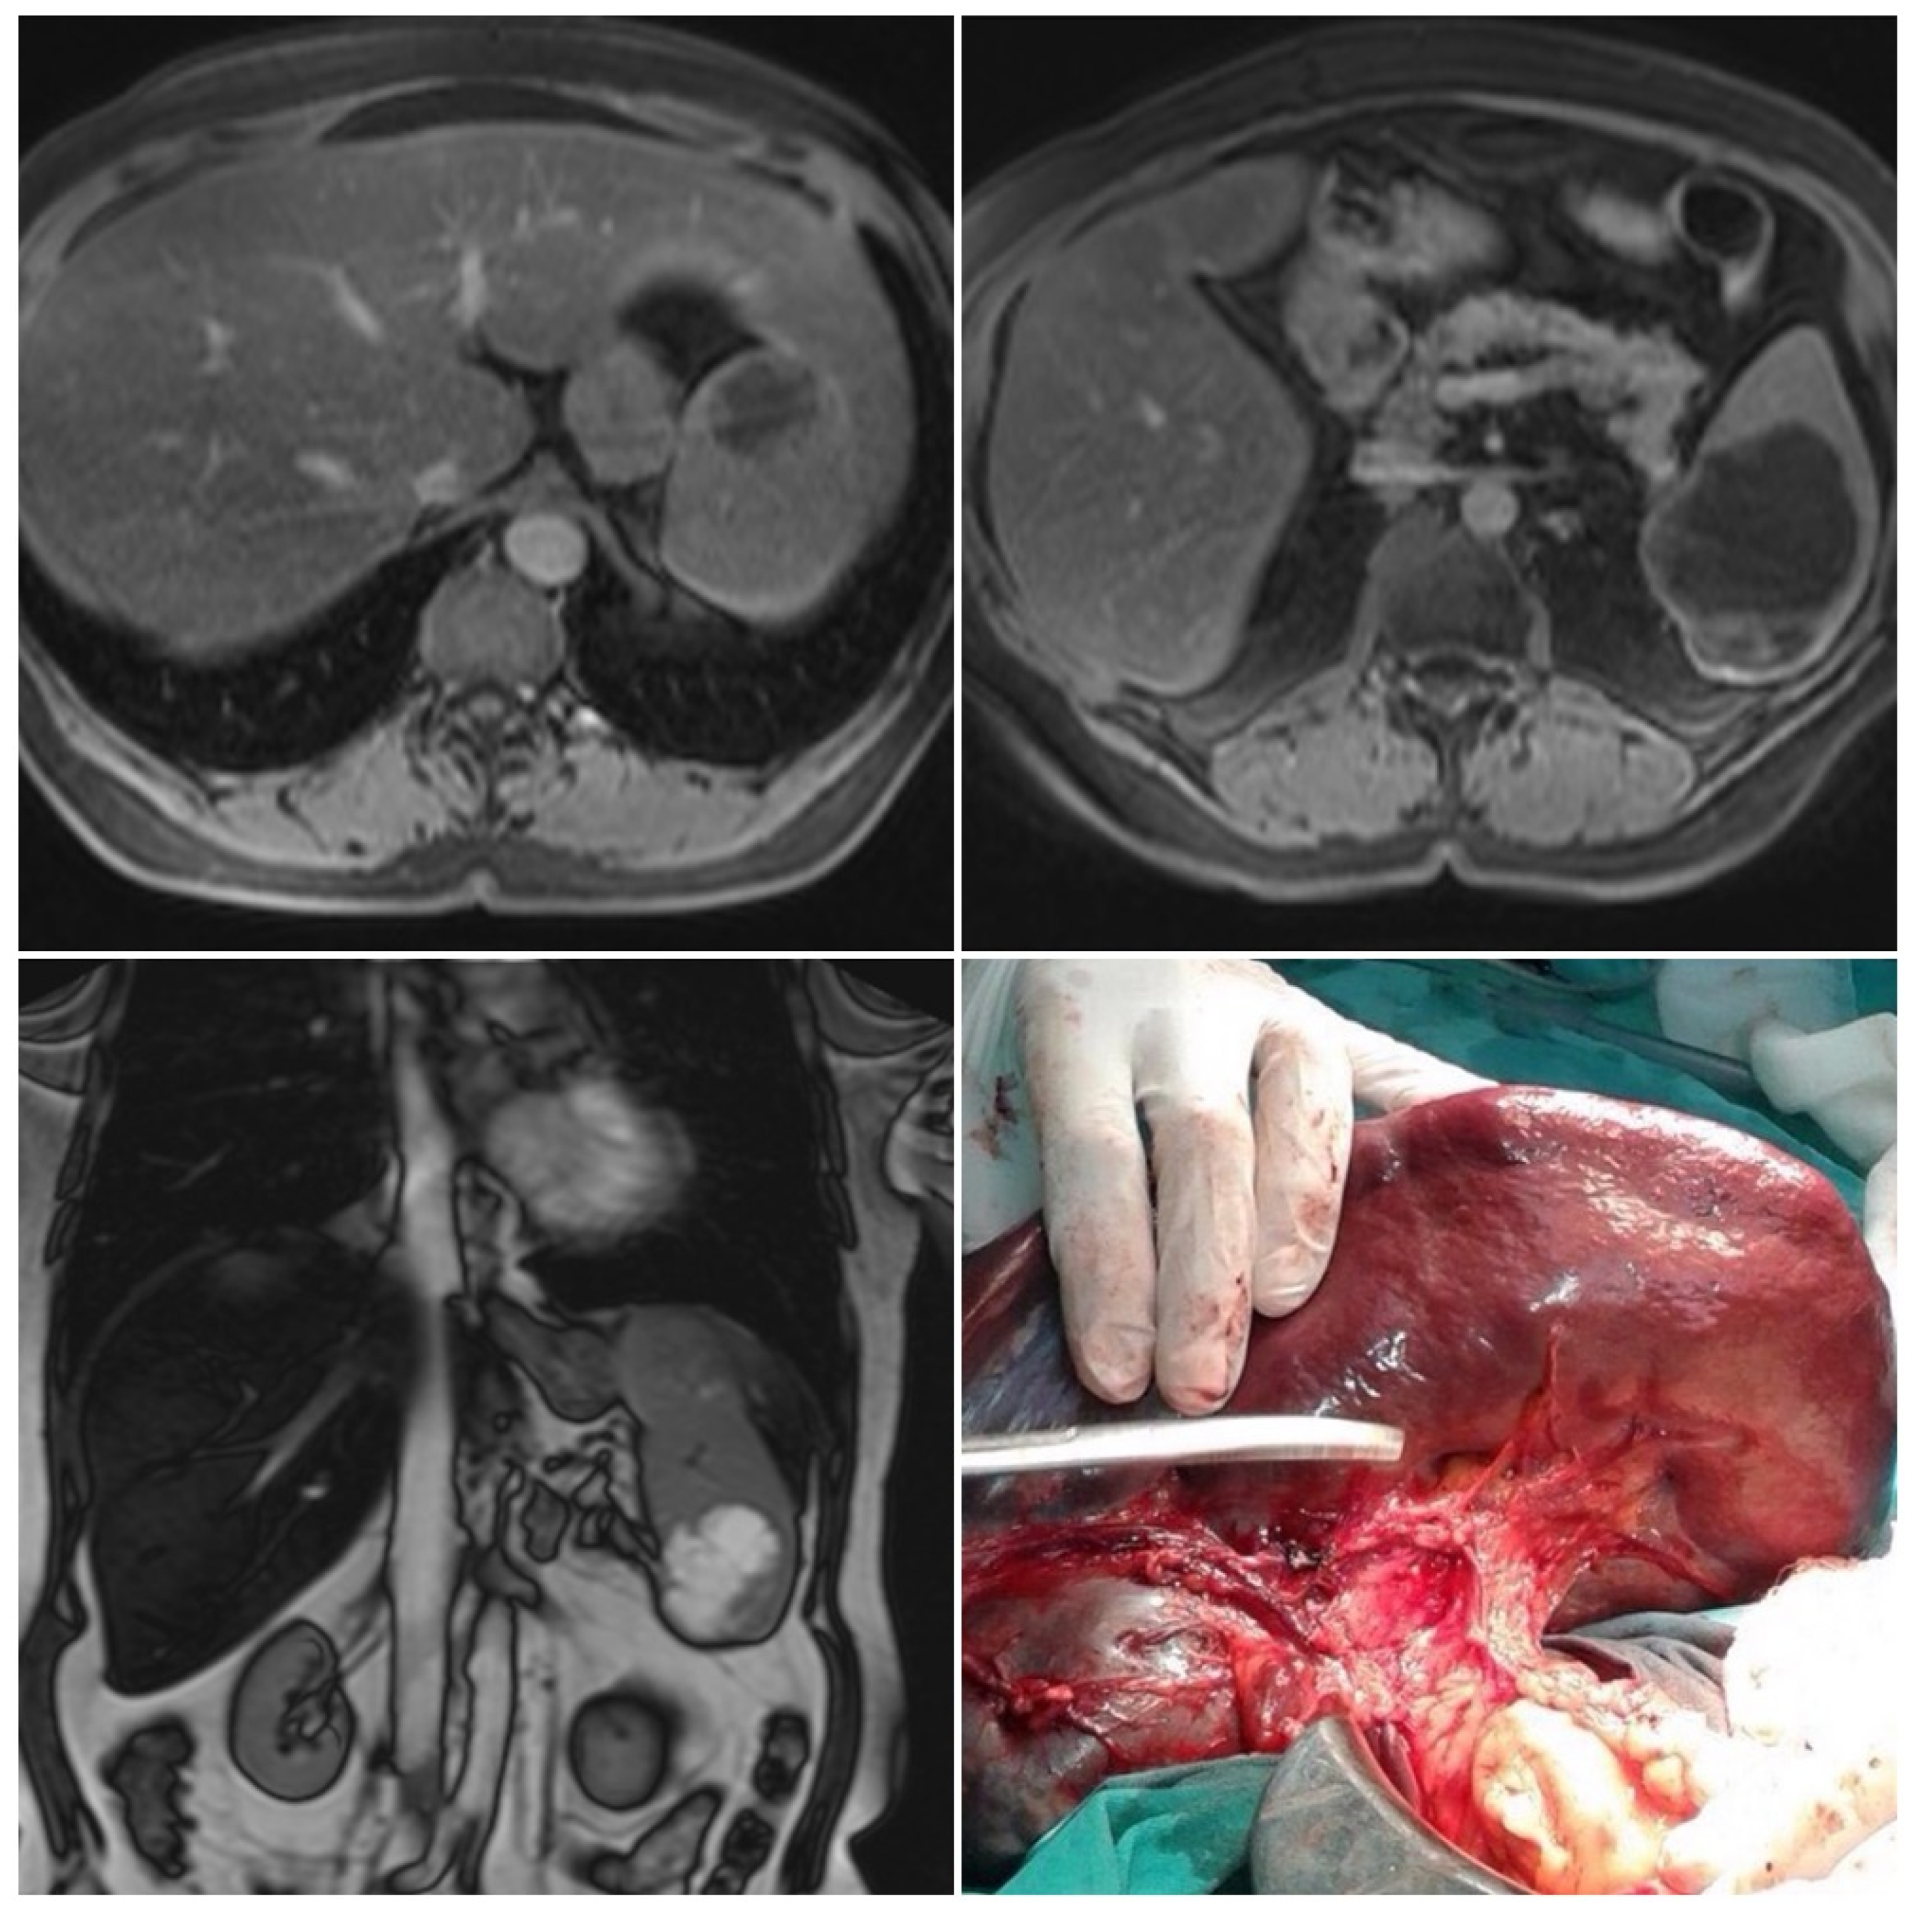

2.5. Imaging Examination

4. Treatment